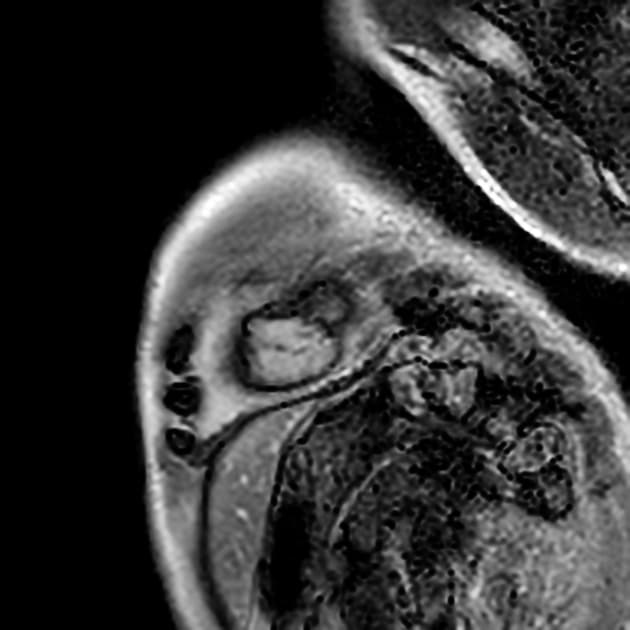

- Bệnh cơ tim phì đại dạng đỉnh thất (apical hypertrophic cardiomyopathy) với tắc nghẽn ở đoạn giữa thất (midventricular obstruction).

- Cả chuỗi hình ảnh LGE và PSIR có tiêm thuốc đối quang (gadolinium) đều cho thấy xơ hóa thành thất dạng ổ (patchy midwall fibrosis), có liên quan đến lớp dưới nội tâm mạc (subendocardial involvement) tại đỉnh thất (apex).

- Necrosis dưới nội tâm mạc ở đỉnh thất (apical subendocardial necrosis) có thể là nguyên nhân gây đau ngực (chest pain).

- "Tắc nghẽn đoạn giữa thất có thể gây tăng áp lực trong buồng tim và thiếu máu cơ tim vùng đỉnh, dẫn đến hoại tử và xơ hóa lớp dưới nội tâm mạc."

- "Hình ảnh tăng sáng muộn (LGE) ở vùng dưới nội tâm mạc đỉnh giúp phân biệt tình trạng này với các nguyên nhân khác gây dày thành tim vùng đỉnh."

Bệnh cơ tim phì đại dạng đỉnh thất là một thể hình thái riêng biệt của bệnh cơ tim phì đại do bất thường sợi co cơ, chủ yếu ảnh hưởng đến đỉnh thất trái. Khác với thể phì đại vách không đối xứng phổ biến hơn, thể này biểu hiện bằng sự dày lên cô lập ở vùng đỉnh, thường dẫn đến tắc nghẽn đoạn giữa thất và tạo gradient áp lực. Tình trạng căng thẳng huyết động này có thể gây thiếu máu cơ tim vùng đỉnh, hoại tử lớp dưới nội tâm mạc và xơ hóa thành thất dạng ổ, như thấy trên hình ảnh cộng hưởng từ tăng sáng muộn. Sự hiện diện của mô xơ liên quan đến nguy cơ cao hơn về rối loạn nhịp và các biến cố tim bất lợi, làm tiên lượng có thể xấu hơn. Chẩn đoán phân biệt bao gồm nhồi máu cơ tim, bệnh cơ tim do amyloid và sarcoid, nhưng hình ảnh đặc trưng dạng 'bích' trên chụp buồng thất trái và sự vắng mặt của bệnh động mạch vành giúp khẳng định chẩn đoán.